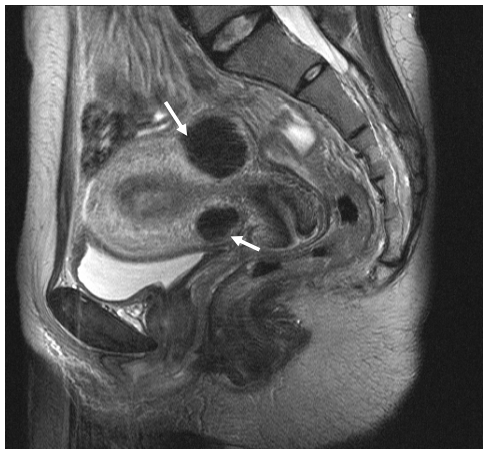

74 35 歲婦女因月經過多(menorrhagia),到醫院求診。經檢查發現輕度貧血及子宮內腫塊。骨盆腔 (pelvis)磁振造影 Sagittal T2-weighted image 顯示兩個子宮腫瘤,如圖示。她最可能罹患:

(A)子宮內膜癌(endometrial carcinoma) (B)子宮頸癌(carcinoma of uterine cervix) (C)子宮肌瘤(uterine myoma) (D)子宮內膜異位(endometriosis)